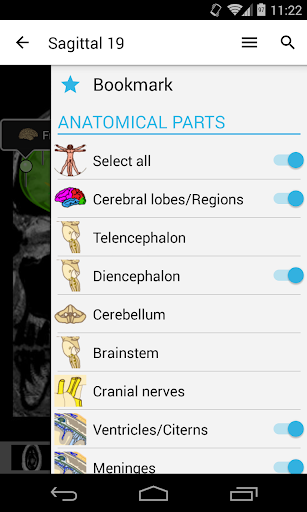

- يمكنك الآن إخفاء الهياكل واحداً تلو الآخر (زر جديد داخل نافذة الوصف المنبثقة) وعرضها مرة أخرى في القائمة الصحيحة